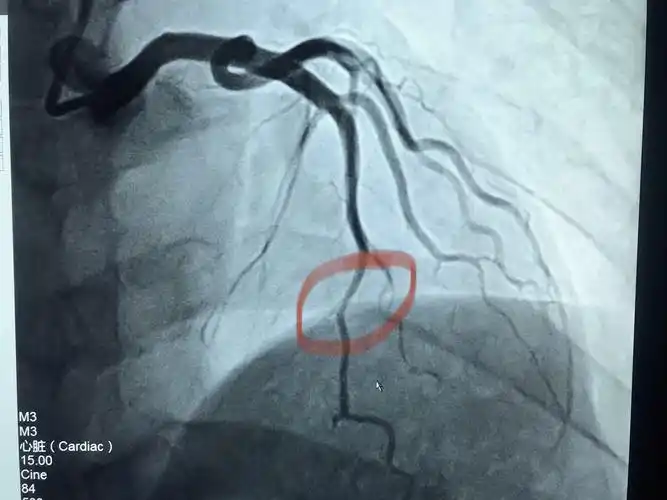

造影狭窄图